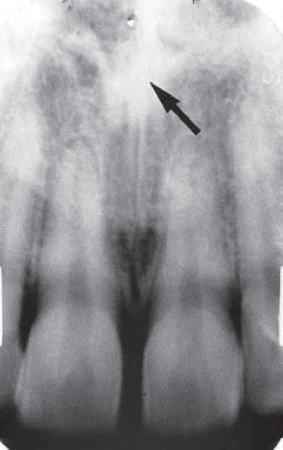

Đường khớp giữa xương hàm trên (còn được gọi là đường khớp giữa) xuất hiện trên phim X quang quanh chóp trong miệng với hình ảnh một đường thấu quang nhỏ giữa hai phần xương tiền hàm. Nó kéo dài từ mào xương ổ răng giữa hai răng cửa giữa, đi lên trên xuyên qua gai mũi trước và tiếp tục đi về phía sau đến mặt sau của khẩu cái cứng. Không phải là bất thường nếu thấy đường khớp thấu quang hẹp này chấm dứt ở mào xương ổ răng với hình tròn nhỏ hoặc hình chữ V mở rộng (xem hình minh hoạ bên dưới). Đường khớp bị giới hạn bởi hai bờ cản quang song song của xương vỏ mỏng mỗi bên xương hàm trên. Vùng thấu quang thường có độ rộng đồng đều. Bờ xương vỏ gần đó có thể trơn láng hoặc hơi không đều nhẹ. Hình ảnh của đường khớp phụ thuộc vào sự khác biệt về mặt giải phẫu và góc độ của tia X khi đi qua đường khớp.